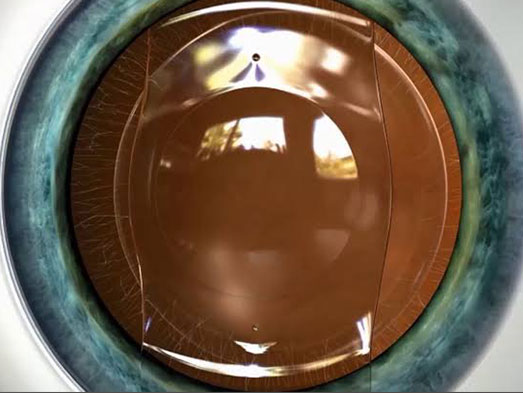

- ICL (Implantable Collamer Lens) – A permanent lens implanted inside the eye to correct vision without altering the cornea.